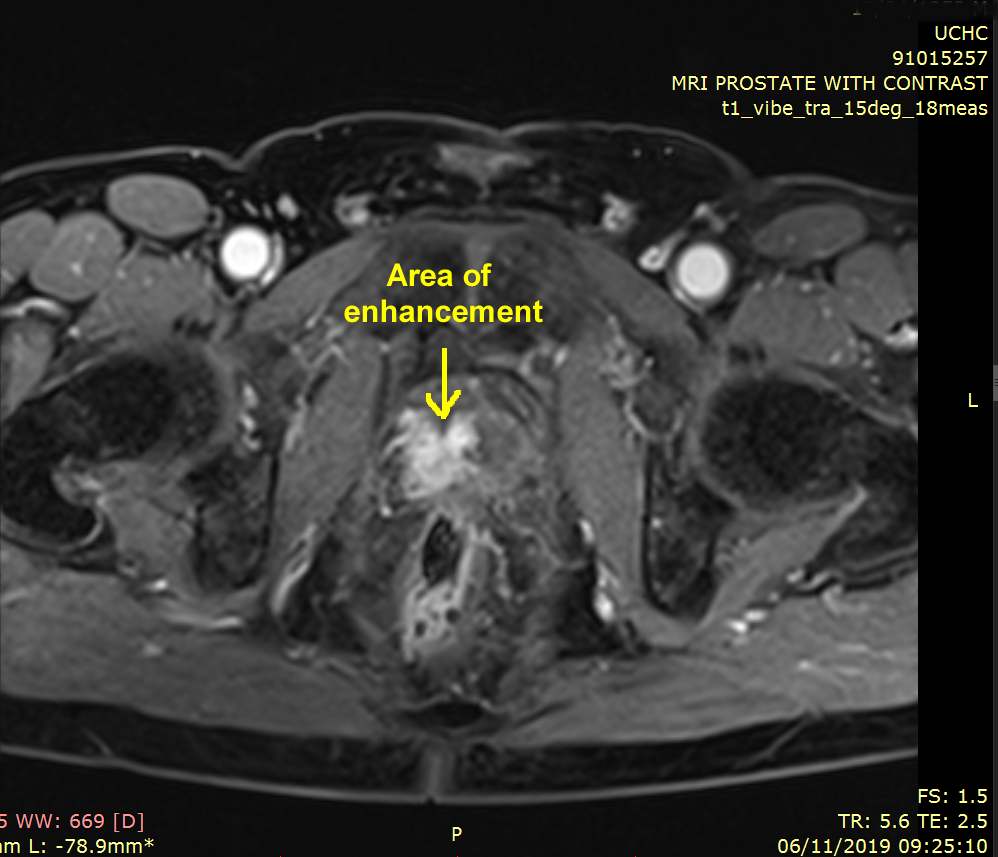

There was Gleason 3+4 disease in anterior and posterior

lesions on the left and both of these were treated at the

same time. Showing the enhancement on image from my November 2019 MRI |